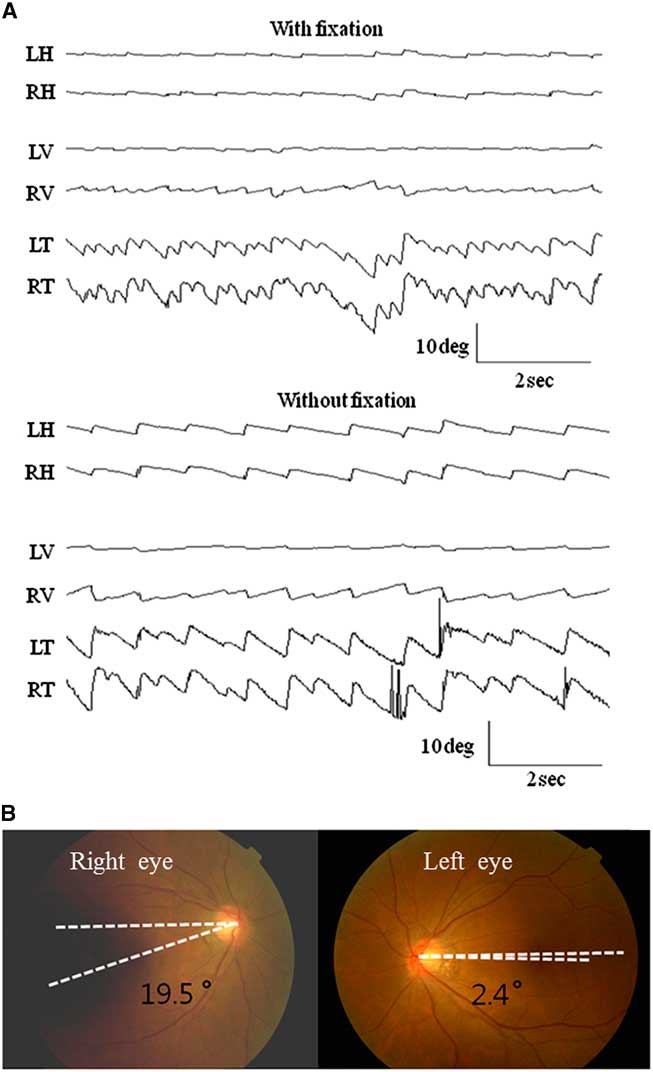

A 44-year-old woman with right LMI was referred for evaluation of oscillopsia and imbalance for 8 months (Figure 1). The oscillopsia was most severe during rightward gaze. She also reported intermittent diplopia and a feeling of tumbling due to upside-down reversal of vision, mostly in the morning. Previous medical records described severe vertigo and imbalance along with left-beating horizontal-torsional nystagmus, right Horner syndrome, and decreased pain and temperature sensation in the right face and left side of the body during the acute phase. Examination at the time of consultation 8 months later additionally showed rightward head tilt and right hypotropia of 5 prism diopters. The spontaneous nystagmus had been changed into ipsiversive torsional (the top poles of the eyes beating toward the right ear) and downbeat. While the intensity of torsional nystagmus was similar in both eyes, the downbeat nystagmus was greater in the hypotropic right eye (Figure 2A). The nystagmus increased without fixation and during rightward gaze. Horizontal head-shaking for 10 seconds induced vigorous right-beating nystagmus and leftward truncal pulsion (see Video). Ipsilesional saccades were hypermetric. Horizontal smooth pursuit was impaired to the right, and vertical smooth pursuit was intruded by nystagmus. Fundus photography showed rightward ocular torsion (Figure 2B, normal range = 0–12.6°; positive values indicate an excyclotorsion), even though the degrees varied due to continuous torsional nystagmus. However, the subjective visual vertical was within the normal range (2.8° with right-monocular viewing, 2.6° with left-monocular viewing, 1.4° with binocular viewing; normal range=–3.1°~–3.0°; positive values indicate rightward torsion from the patient’s perspective). The initial and follow-up magnetic resonance images (MRIs) at the time of consultation showed an infarction restricted to the caudal and middle portions of the right lateral medulla without interval changes (Figure 1). The oscillopsia, nystagmus, and imbalance persisted over the following two years without a response to gabapentin up to 2,700 mg per day.

Figure 2 A) Oculography of the spontaneous nystagmus. The patient shows spontaneous nystagmus beating rightward, downward (4.8±1.8 in the right eye and 1.1±0.6 °/s in the left eye), and clockwise (10.9±3.2°/s in the right eye and 9.3±1.4°/s in the left eye, the upper pole of the eyes beating to the right ear) without fixation. The nystagmus increases without fixation. Note the greater downbeat nystagmus in the right eye. LH, horizontal position of the left eye; RH, horizontal position of the right eye; LV, vertical position of the left eye; RV, vertical position of the right eye; LT, torsional position of the left eye; RT, torsional position of the right eye. Upward deflection indicates rightward, upward, and clockwise (from the patient’s perspective) eye motion. B) Ipsiversive rightward ocular torsion is evident on fundus photography (normal range: 0 ~12.6°, Positive values indicate extorsion of the eyes).